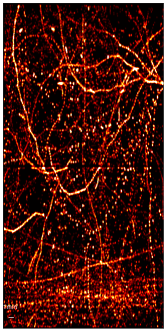

Figure 3: SR images of the test dataset, i.e., the last 100 frames of a simulation video from the challenge dataset obtained from (a) Ground Truth (b) DETR and (c) DE-DETR.

The mAP and mAR for DETR are: 80.12% and 55.17% and for DE-DETR they are: 87.60% and 63.79%. The super-resolution maps are generated using a proper Gaussian around each MB location and shown for comparison in Figure 3.